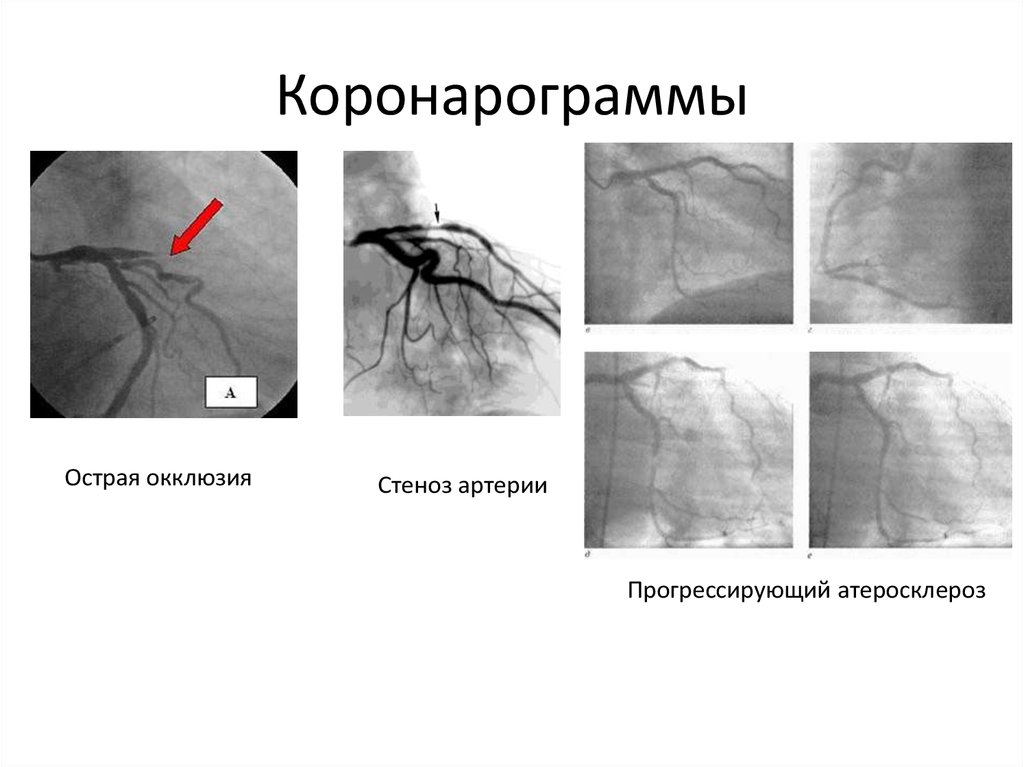

Хроническая окклюзия артерий: причины, симптомы и лечение